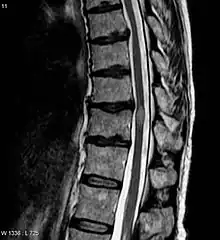

The most common initial manifestation of the disease is inflammation of the spinal cord (myelitis).[4] Myelitis causes spinal cord dysfunction, which can result in muscle weakness, paralysis in the limbs, lost or reduced sensation, spasms, loss of bladder and bowel control, or erectile dysfunction.[1][4][2][7][8][9] The myelitis can be transverse, affecting an entire cross-section of the spinal cord, and showing bilateral symptoms.

In NMOSD, areas of brain tissue that appear normal in conventional magnetic resonance imaging (MRI) can show damage in diffusion tensor imaging (DTI), although less so compared to multiple sclerosis (MS).[25]

Most research into the pathology of NMO has focused on the spinal cord. The damage can range from inflammatory demyelination to necrotic damage of the white and grey matters. The inflammatory lesions in NMO have been classified as type II lesions (complement-mediated demyelination), but they differ from MS pattern II lesions in their prominent perivascular distribution. Therefore, the pattern of inflammation is often quite distinct from that seen in MS.[18][26]

The clinical course and the response to therapy is different for various diseases classed within these groups, showing a better prognosis for those in the NMO-Ab(−)/MOG-Ab(−) group, and a worse prognosis for those in the NMO-Ab(+)/MOG-Ab(+) group.[30] The MOG-related NMO can be radiologically identified by the conus involvement. Myelin-oligodendrocyte glycoprotein antibody–positive patients were more likely to have conus involvement on spinal magnetic resonance imaging.[31]

| Acute myelitis | intramedullary lesion > 3 contiguous segments, or spinal atrophy ≥ 3 contiguous segments |